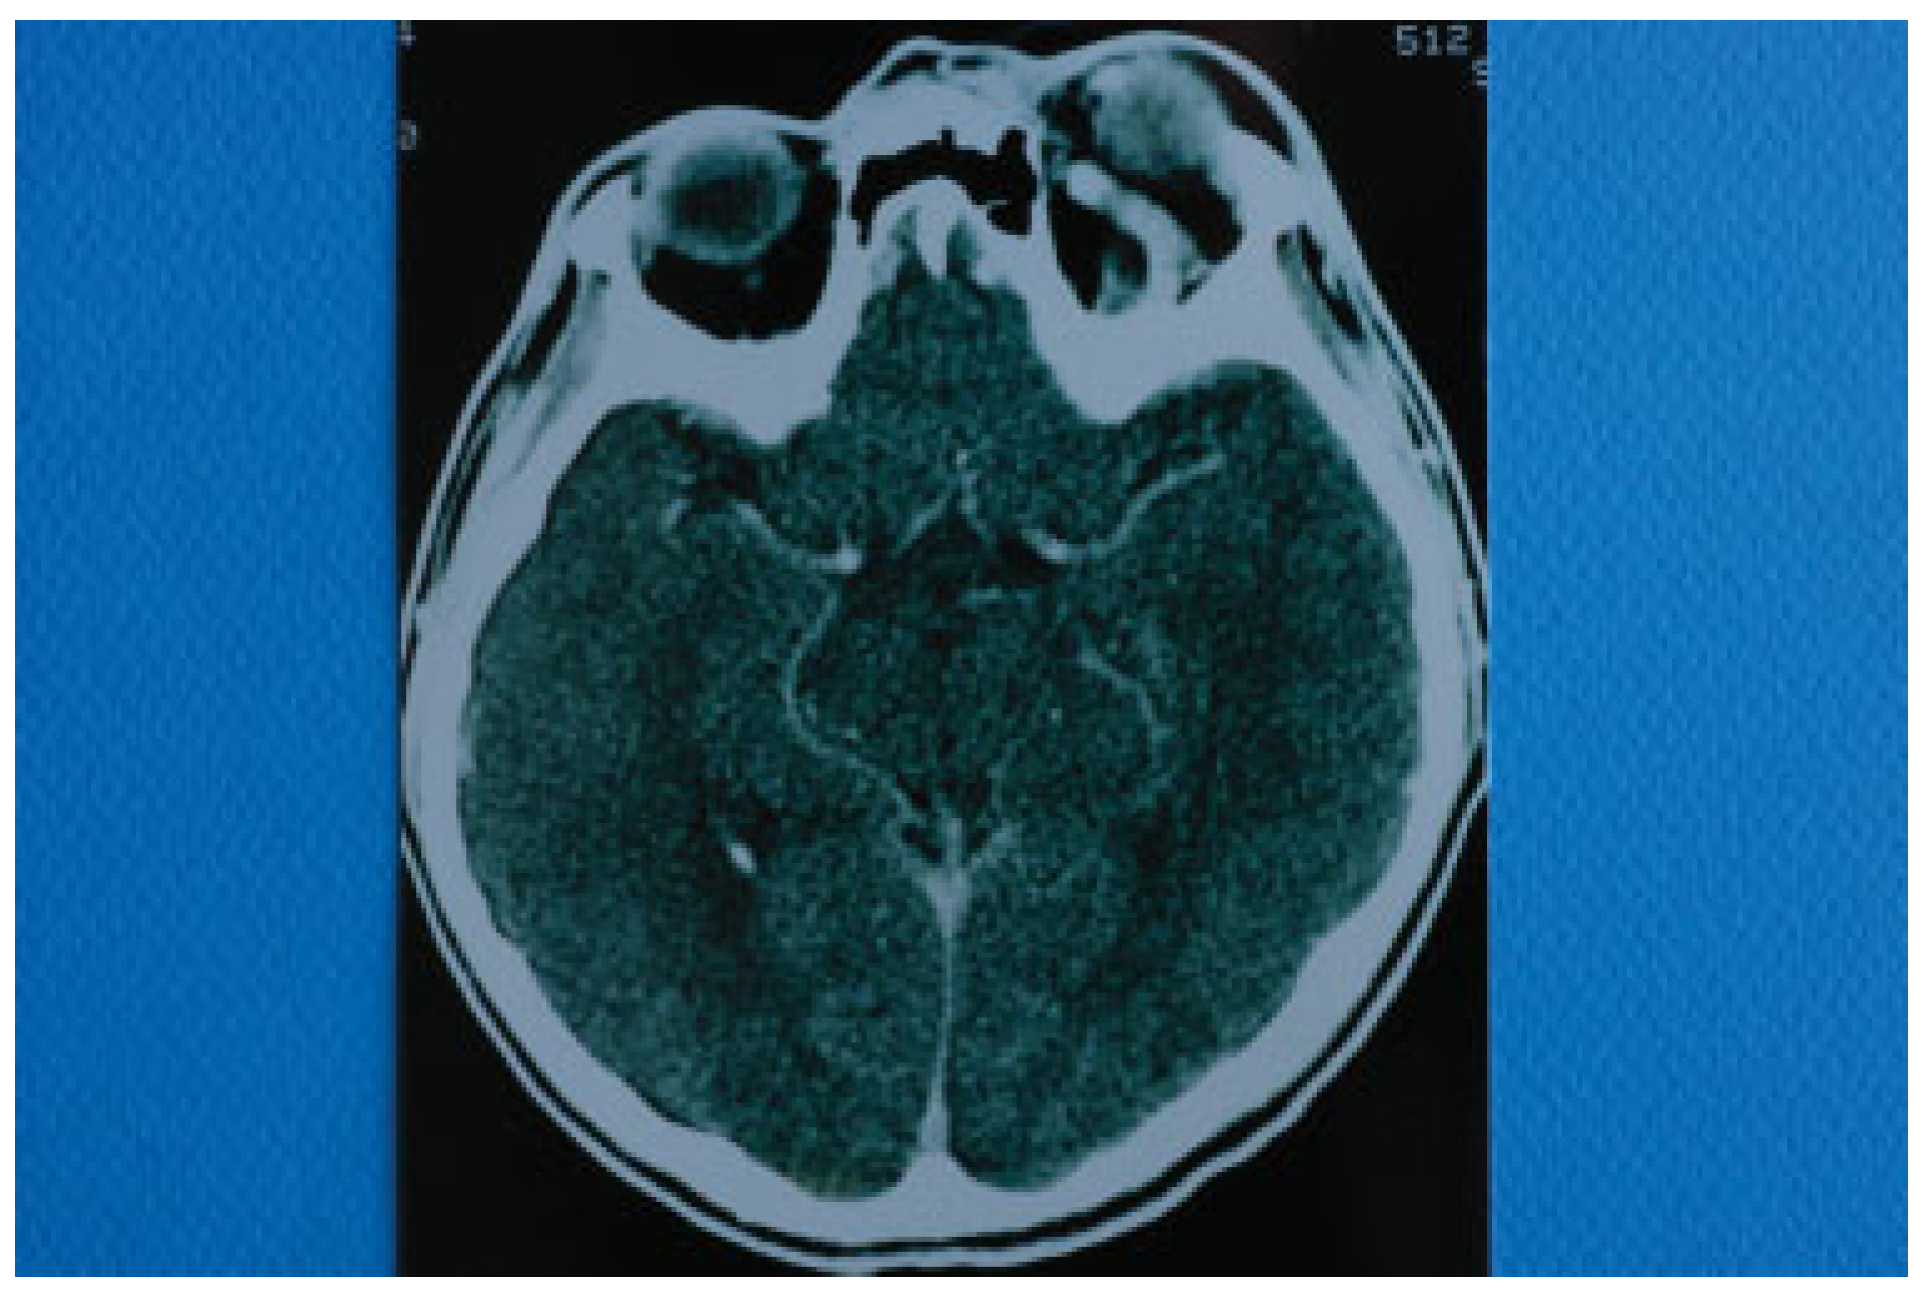

Figure 7. Schematic drawing showing the anatomic continuity of the cavernous sinus, the orbital apex, and the superior orbital fissure. Posttraumatically, each of these structures may be involved with similar clinical manifestations. Cranial nerves III, IV, VI, and V1 pass through both the cavernous sinus and the superior orbital fissure to enter the orbit. This is the reason why diplopia, ophthalmoplegia, ptosis of the upper lid, mydriasis, and frontal sensory loss are common manifestations. Maxillary division of the trigeminal nerve passes through the cavernous sinus but not through the superior orbital fissure. (It exits the cranium through foramen rotundum). This is the reason why sensory loss of infraorbital area, nose, and upper lip is not a symptom of superior orbital fissure syndrome. Sympathetic fibers travel with the internal carotid artery which does not pass through the superior orbital fissure and this is the reason why if miosis and Horner syndrome is clinically detected, one should suspect cavernous sinus syndrome or carotid-cavernous fistula. (1) Mandibular division of trigeminal nerve, (2) maxillary division of trigeminal nerve, (3) cav- ernous sinus, (4) optic nerve, (5) internal carotid artery traveling through cavernous sinus, (6) oculomotor nerve, (7) trochlear nerve, (8) abducens nerve, (9) ophthalmic division of trigeminal nerve, (10) ophthalmic artery exiting through optic foramen, (A) optic foramen, (B) superior orbital fissure, and (C) cavernous sinus.